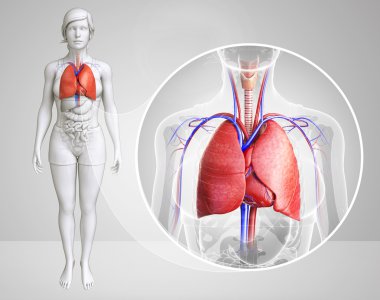

çizim, pulmoner dolaşım

ArkaplankişiİnsanKadınkanİlaçSolunumAvrupa DiliKardiyolojikalpdüzresim çalışmasıAkciğerSistemkemergemiüstünvenanatomiNormalauricletedavülarterAzalanyükselenCavaaortvena cavatorasikaşağıPulmonerventrikül20 30 yıldüz arka planKan damarıSolunum SistemiKan dolaşımıPnömolojiaortik kemerinen aortPulmoner dolaşımtorasik aortyükselen aortaPulmoner arterBenzer İçerikler